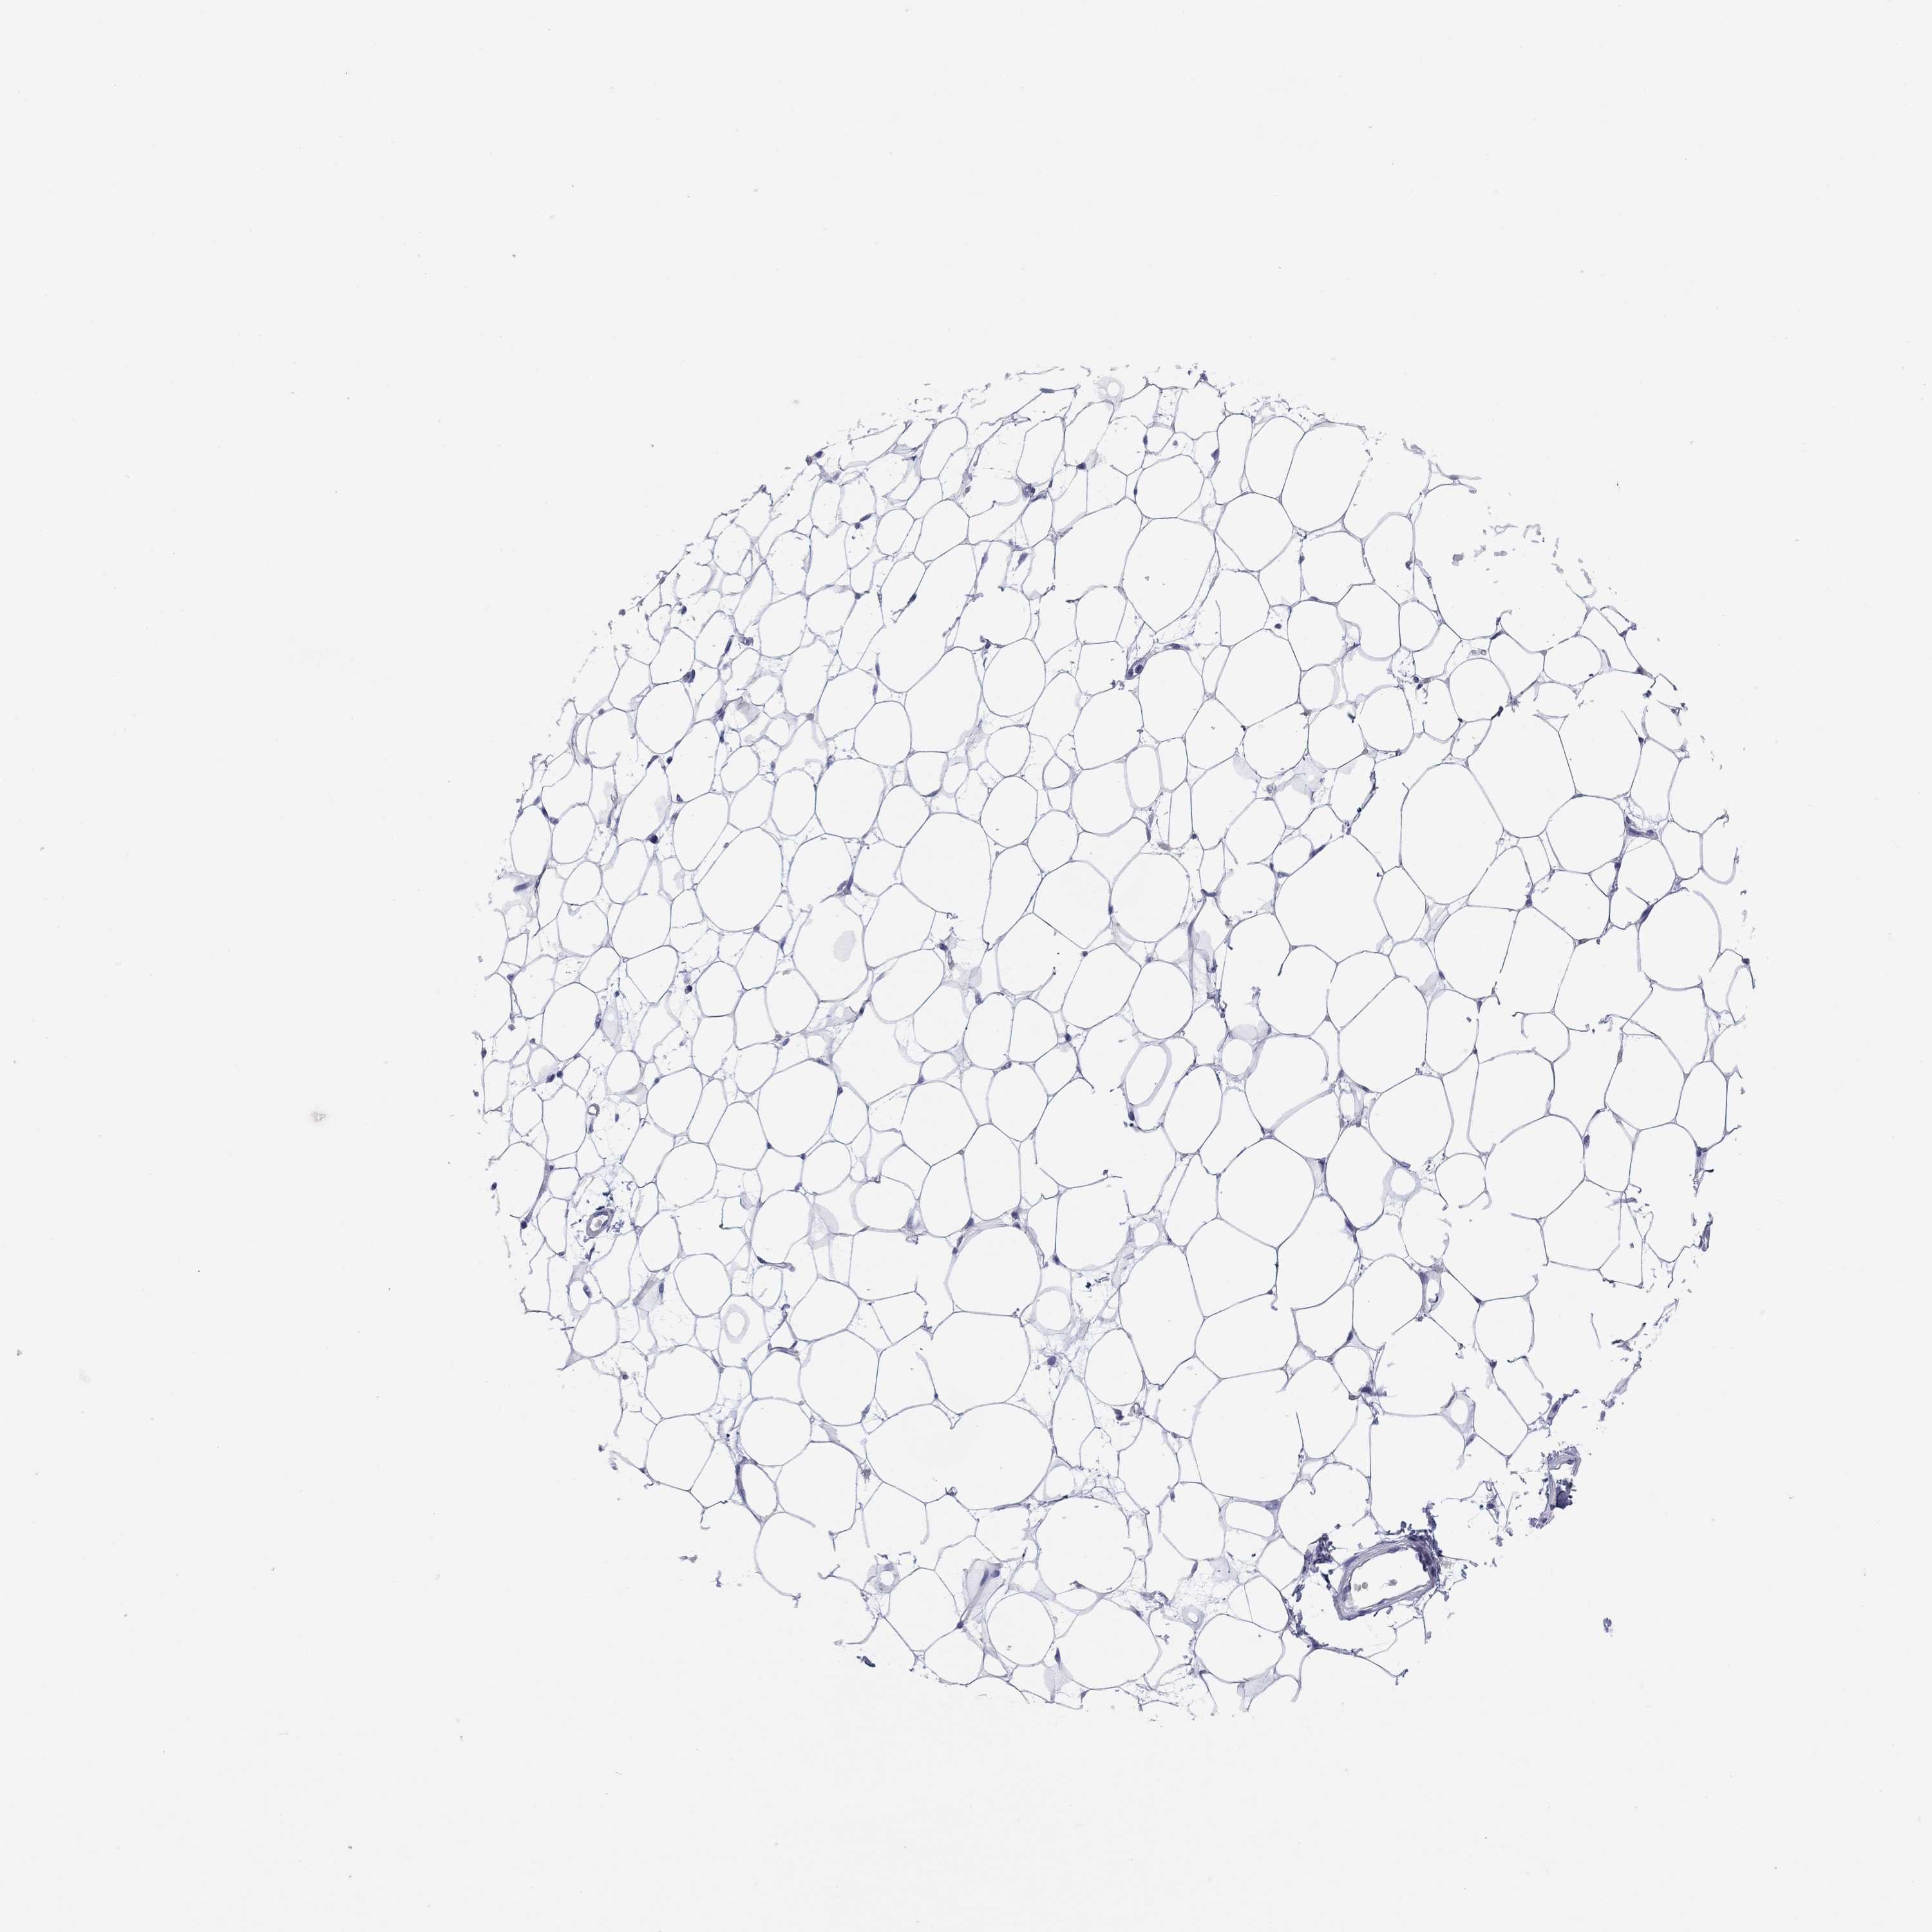

BREAST - Antibody stainingi

Antibody staining in the annotated cell types in the current human tissue is reported as not detected, low, medium, or high, based on conventional immunohistochemistry profiling in selected tissues. This score is based on the combination of the staining intensity and fraction of stained cells.

Each image is clickable and will lead to virtual microscopy that enables deeper exploration of all samples and also displays staining intensity scores, fraction scores and subcellular localization as well as patient and tissue information for each sample.

Antibody HPA031636Antibody HPA076665

Adipocytes Not detectedNot detected

Glandular cells Not detectedNot detected

Myoepithelial cells Not detectedNot detected